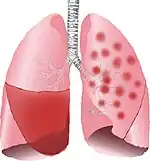

![]() | |

Typical distribution of lobar pneumonia (left in image) and bronchopneumonia (right in image) | |